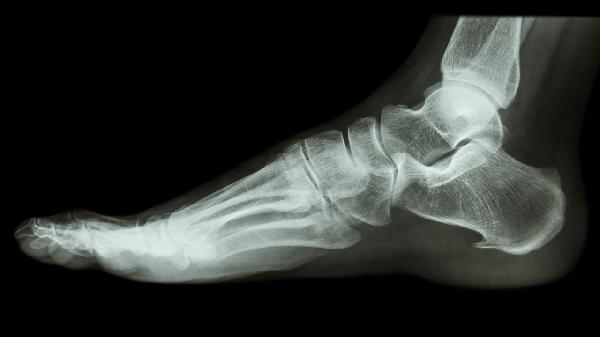

脚趾骨折45天后能否走路需根据愈合情况判断,若复查显示骨痂形成良好且无疼痛肿胀,通常可以逐渐恢复行走。若存在愈合延迟或固定不稳,过早负重可能导致二次骨折。

骨折后45天是否达到临床愈合标准与损伤程度、年龄、营养状况等因素相关。单纯线性骨折且接受规范固定者,此时骨痂已初步形成,在医生指导下可尝试部分负重行走,初期建议使用拐杖分担压力,选择硬底鞋提供支撑,避免跑跳或长时间站立。康复期间应定期复查X线,观察骨痂生长是否连续、对位是否良好。

开放性骨折、粉碎性骨折或伴有血管神经损伤者,愈合周期往往延长至8-12周。若过早拆除外固定或过度负重,可能造成骨折线移位甚至内固定物断裂。糖尿病患者、骨质疏松患者及吸烟人群更需谨慎,这类人群骨再生能力较弱,二次骨折风险显著增加。如行走时出现局部刺痛、肿胀加剧或异常活动感,应立即停止负重并就医。